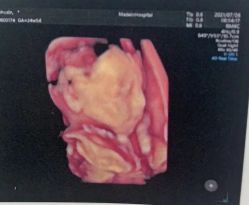

• 美德因妇儿医院

• -美德因妇儿医院

热情聪慧哗哗蝉 上传于 22-02-28 | 报错

天气丹 上传于 22-02-27 | 报错